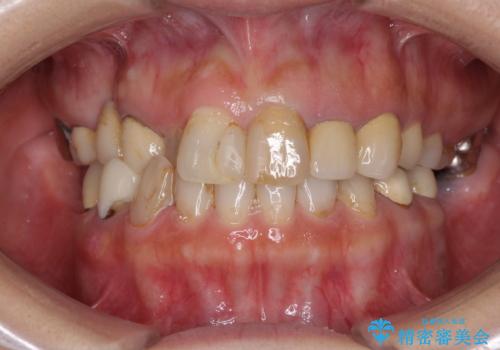

- 上顎の前から2番目の歯の古い樹脂をセラミックにしたいといらっしゃった方の症例です。

古い樹脂を除去後、オールセラミッククラウンによる補綴を行いました。

- オールセラミッククラウン…¥100,000×2、仮歯…¥10,000×2費用は治療当時の料金となります